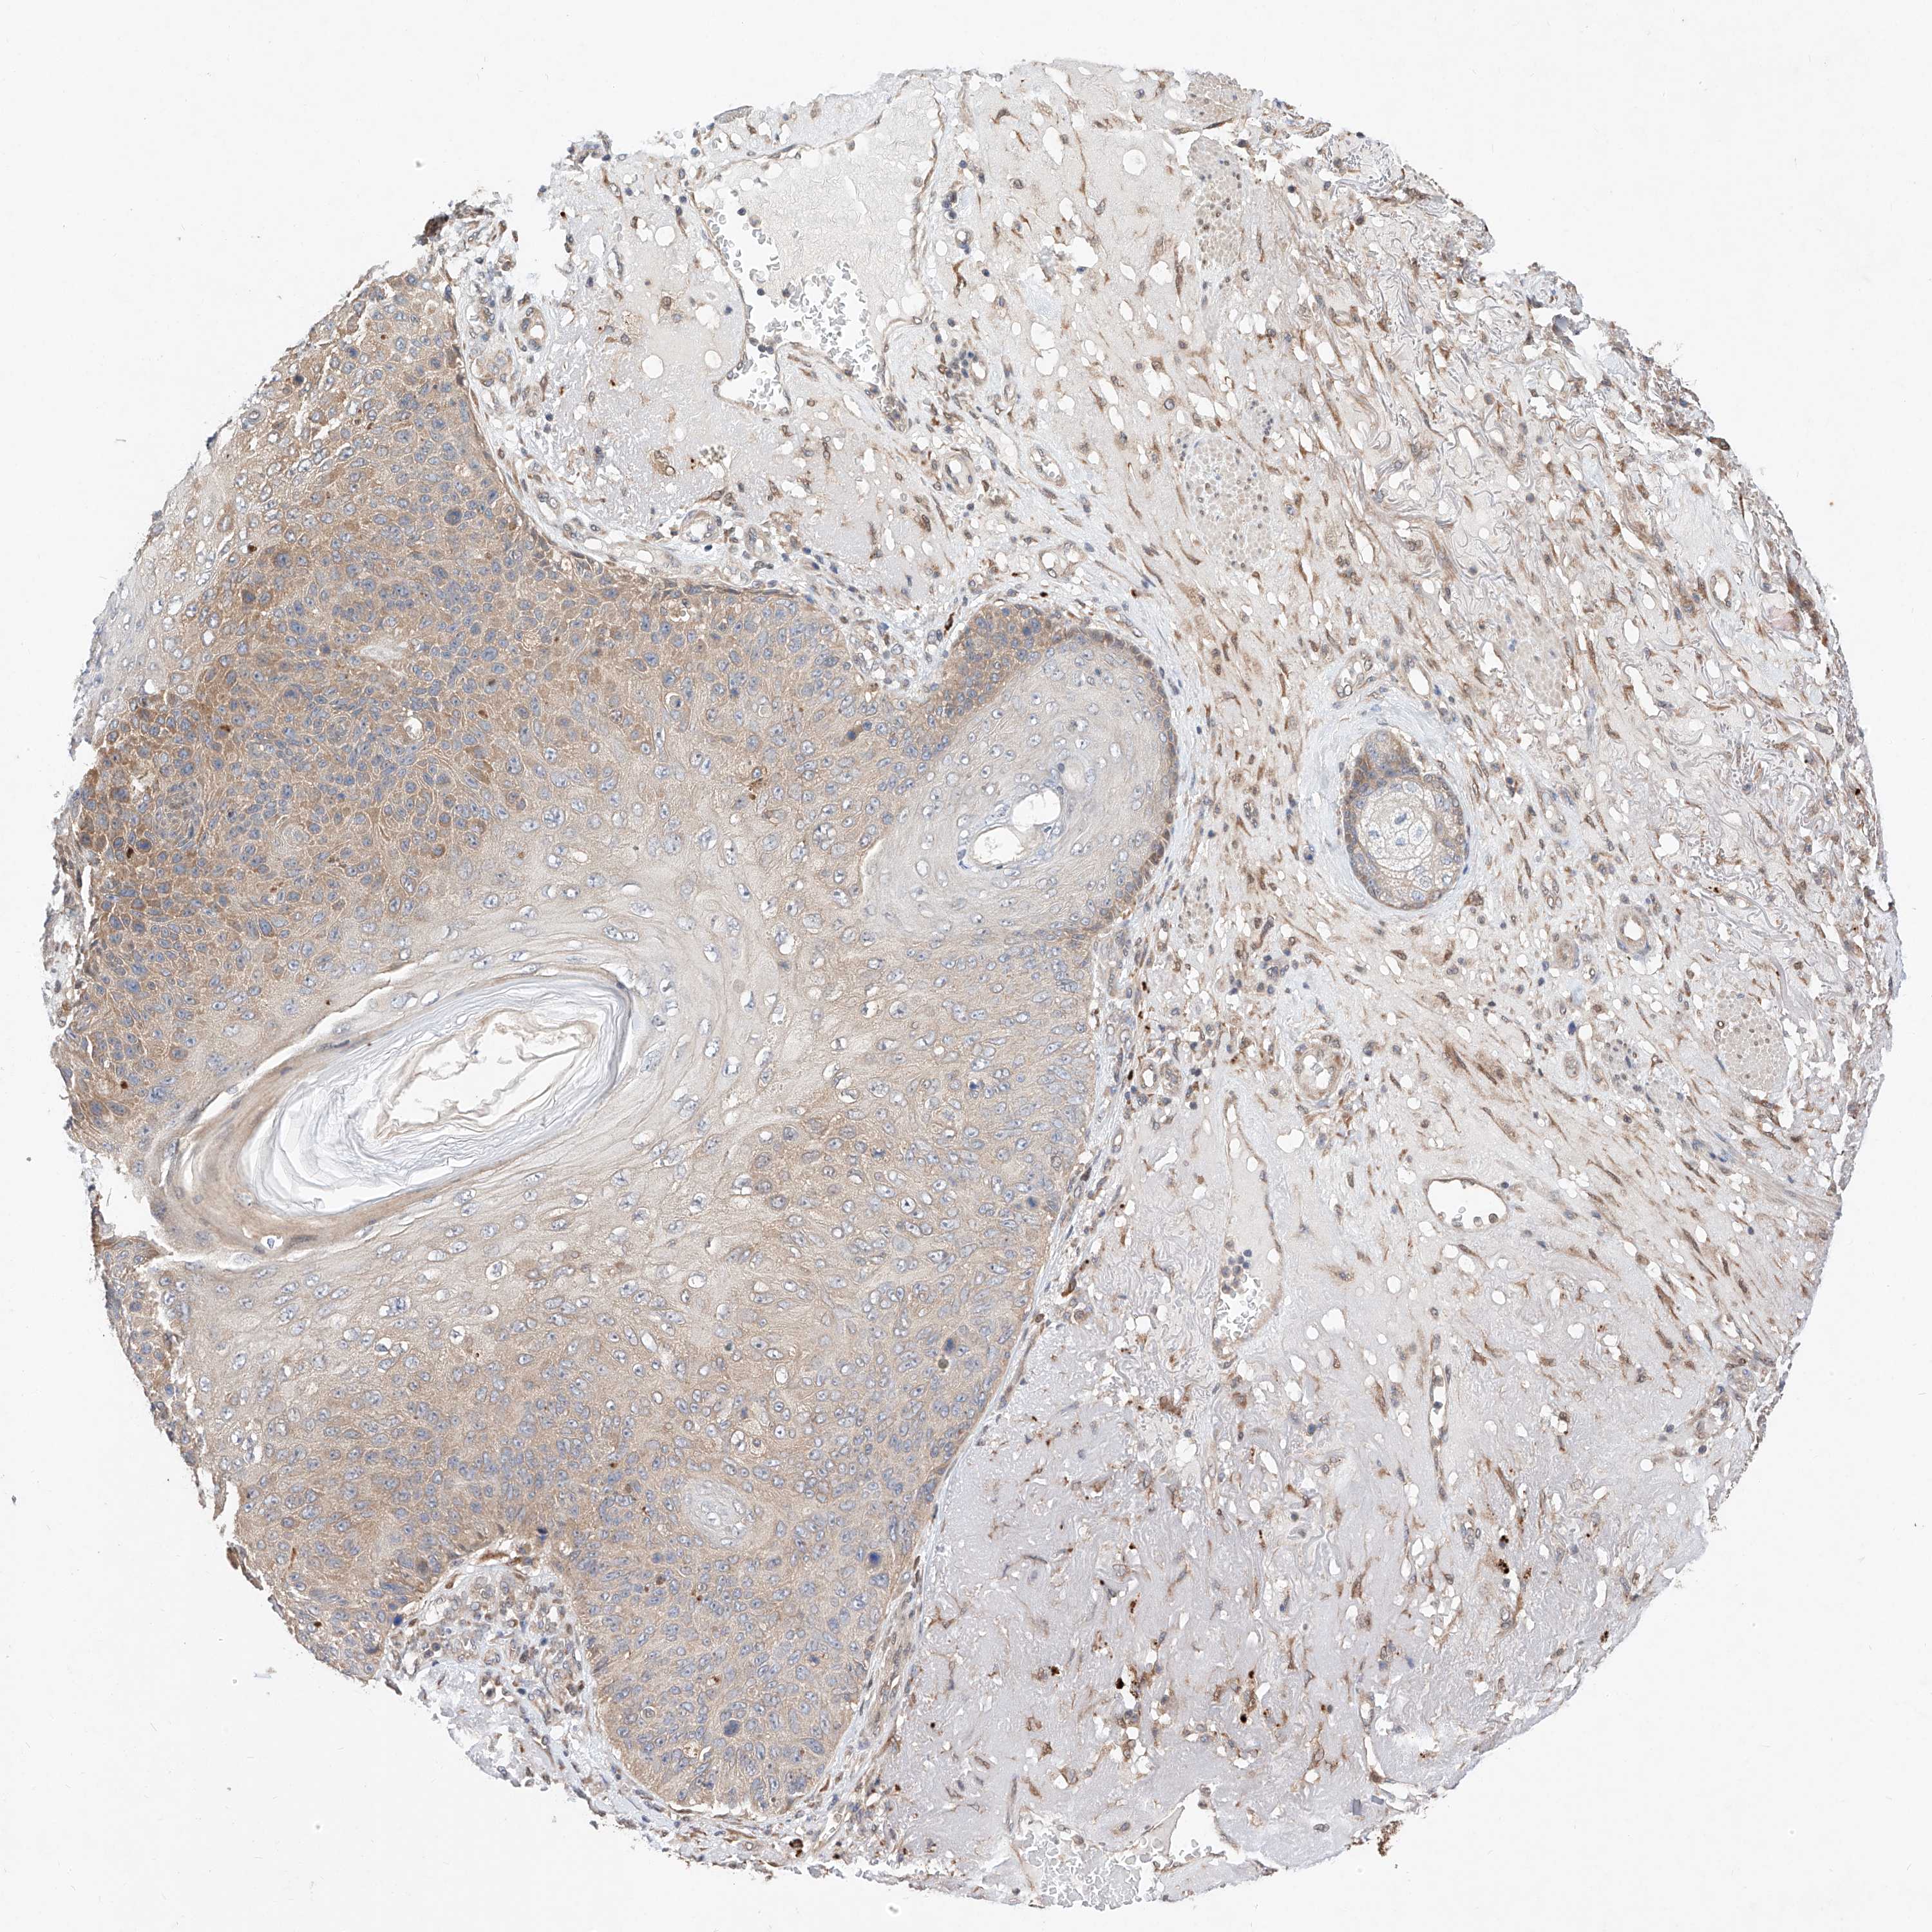

CANCER SKIN CANCER Show tissue menu

Basal cell and squamous cell cancer

SKIN CANCER - Protein expressioni

A mouse-over function shows sample information and annotation data. Click on an image to view it in a full screen mode. Samples can be filtered based on level of antibody staining by selecting one or several of the following categories: high, medium, low and not detected. The assay and annotation is described here.

Each image is clickable and will lead to virtual microscopy that enables deeper exploration of all samples and also displays staining intensity scores, fraction scores and subcellular localization as well as patient and tissue information for each sample.

Antibody HPA006491

Staining

High

Medium

Low

Not detected

Intensity

Strong

Moderate

Weak

Negative

Quantity

>75%

75%-25%

<25%

None

Location

Nuclear

Cytoplasmic/membranous

Cytoplasmic/membranous,nuclear

Basal cell carcinoma

Squamous cell carcinoma, NOS

Squamous cell carcinoma, metastatic, NOS